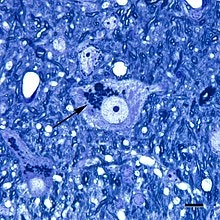

Lipofuscin

Lipofuscin is a "yellow-brown pigment" that is the byproduct of "the oxidation of unsaturated fatty acids", aka seed oil decay.

Decomposing seed oils mix with iron, aluminum, and other oxidized garbage to produce this suspicious substance